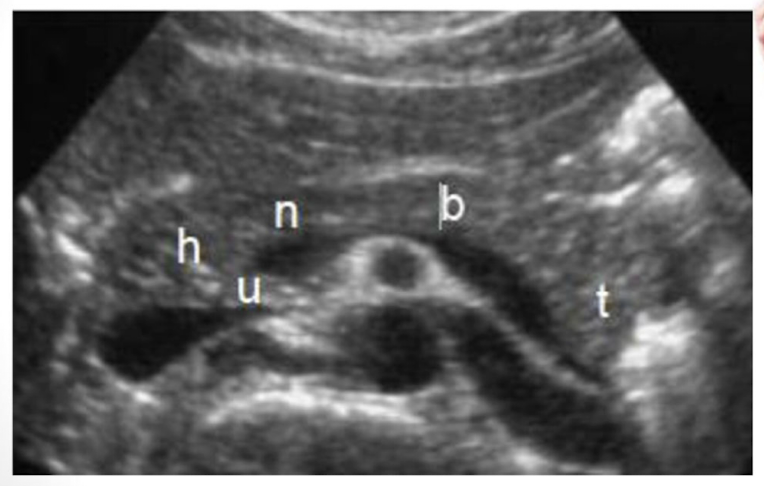

Be able to identify this image taken in a transverse plane

label this image

label

identify all structures

A) left liver lobe

B) gastroduodenal artery

C) common bile duct

D) Main portal confluence

E) Splenic vein

F) SMA

G) IVC

H) Aorta